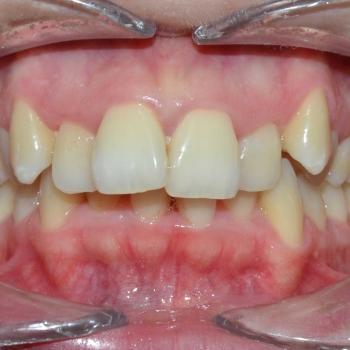

Tünde a felső fogív torlódása, illetve az alsó metszőfogak között található rések miatt keresett fel. Az első találkozásunk alkalmával azonban fény derült a középvonalak eltolódására, enyhe mélyharapásra, a felső metszőfogak túlzott elülső pozíciójára, illetve a régóta hiányzó alsó 6-os fog helyének beszűkülésére is, így a kezelési terv ezen problémák megoldására is kitért.